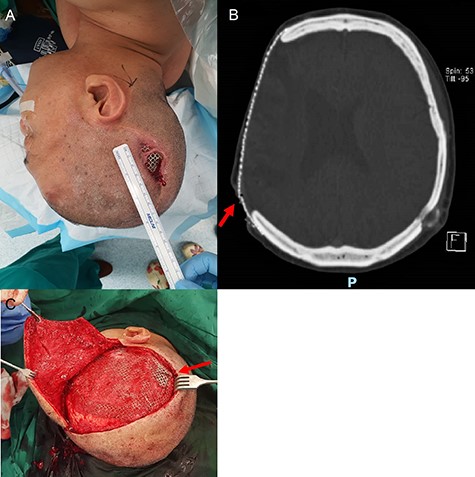

A 54-year-old man presented with a three-month history of a right parietal scalp wound, measuring 5 × 2.5 cm, with exposed titanium mesh (Fig. 1A). He had a post-traumatic decompressive craniectomy and titanium mesh cranioplasty 18 years ago. A computed tomography scan of the brain did not reveal any underlying collection and showed the configuration of the titanium mesh which resulted in the exposure (Fig. 1B). He was counselled for and underwent wound exploration, implant removal and exchange, and bipedicled flap reconstruction.

Parietal scalp wound with an exposed implant. A 54-year-old man presented with a right parietal scalp wound measuring 5 × 2.5 cm, with exposed titanium mesh cranioplasty implant (A). Computed tomography showed outward tenting of the implant beneath the area of exposure (B). This was correlated intraoperatively, due to venting cuts made from the initial surgery (C). This had likely caused pressure on the overlying skin and resulted in skin breakdown and implant exposure.

Intraoperatively, venting cuts in the mesh were noted (Fig. 1C), which had likely caused pressure on the overlying skin, resulting in breakdown and implant exposure. Most interestingly, there was a layer of epithelium with hair follicles and surrounding granulation directly beneath the area of an exposed implant (Fig. 2). This was excised and sent for histopathology, which revealed dermal appendages including pilosebaceous units and eccrine glands, associated with prominent chronic inflammation (Fig. 3).